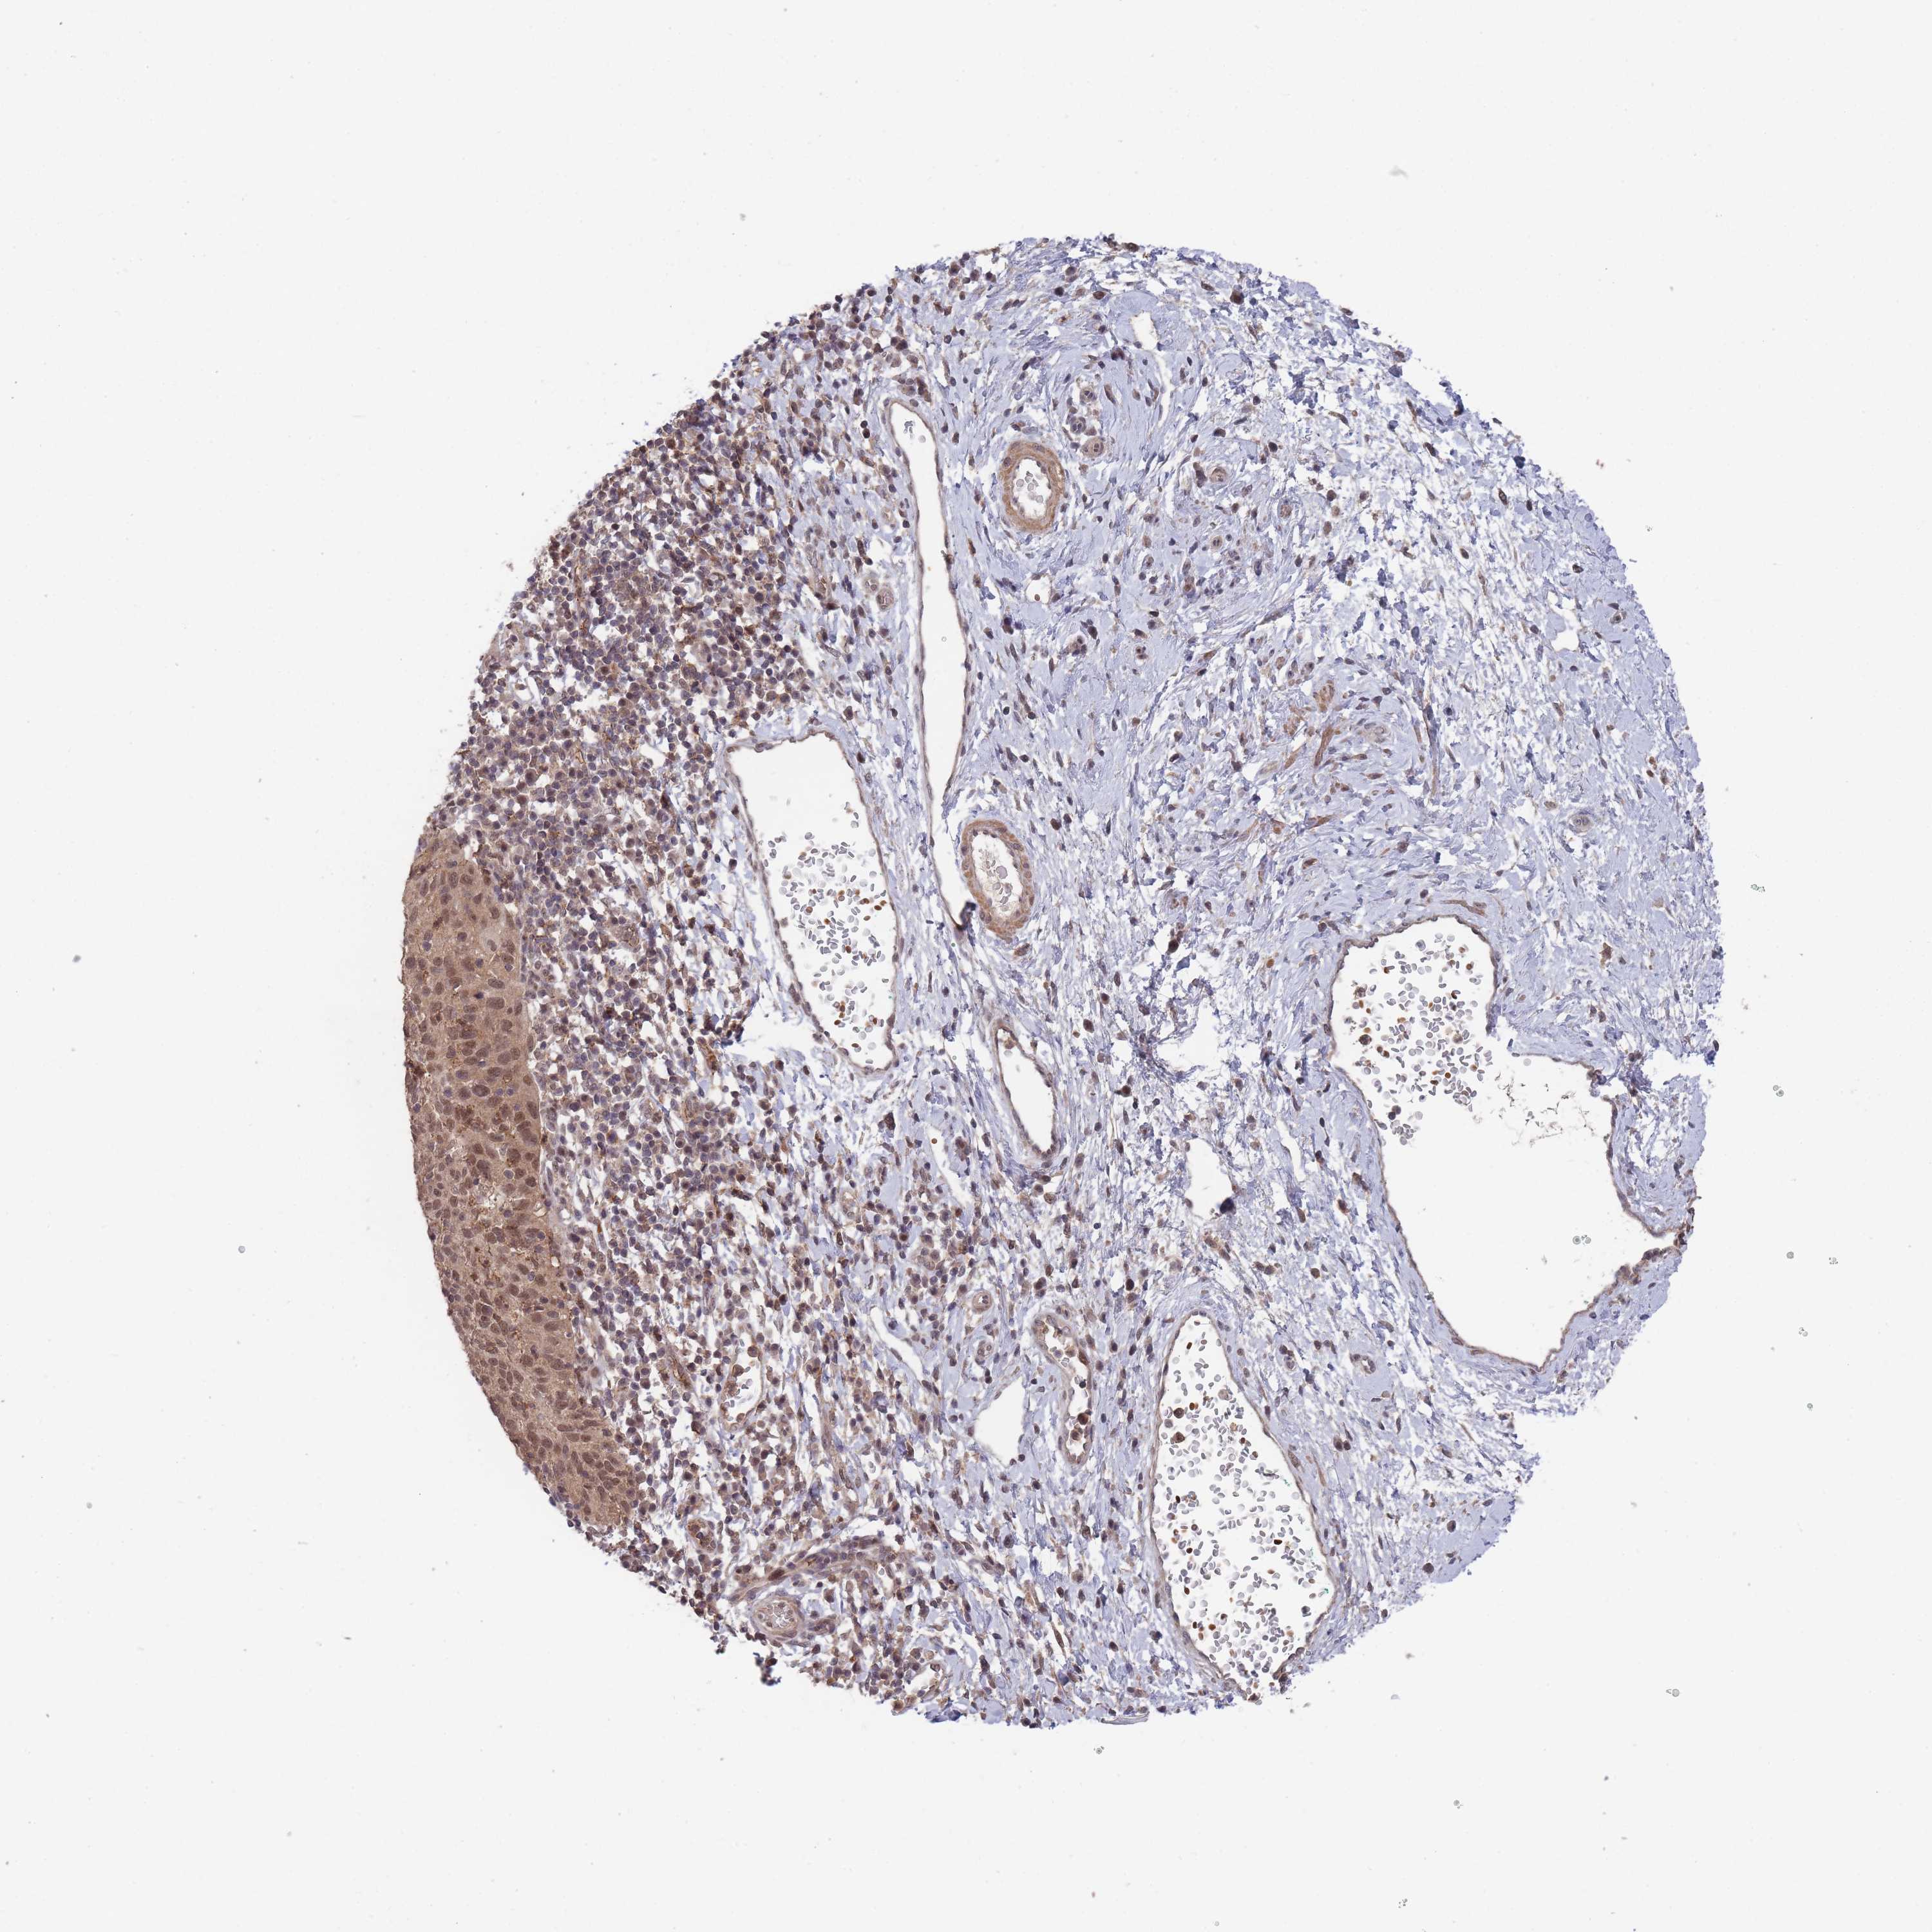

CERVICAL CANCER - Protein expressioni

A mouse-over function shows sample information and annotation data. Click on an image to view it in a full screen mode. Samples can be filtered based on level of antibody staining by selecting one or several of the following categories: high, medium, low and not detected. The assay and annotation is described here.

Note that samples used for immunohistochemistry by the Human Protein Atlas do not correspond to samples in the TCGA dataset.

Antibody stainingi

Antibody staining in the annotated cell types in the current human tissue is reported as not detected, low, medium, or high, based on conventional immunohistochemistry profiling in selected tissues. This score is based on the combination of the staining intensity and fraction of stained cells.

Each image is clickable and will lead to virtual microscopy that enables deeper exploration of all samples and also displays staining intensity scores, fraction scores and subcellular localization as well as patient and tissue information for each sample.

Antibody HPA050275

Staining

High

Medium

Low

Not detected

Intensity

Strong

Moderate

Weak

Negative

Quantity

>75%

75%-25%

<25%

None

Location

Nuclear

Cytoplasmic/membranous

Cytoplasmic/membranous,nuclear

Squamous cell carcinoma, NOS